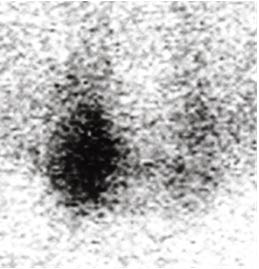

Neck ultrasonography demonstrated two heterogeneous nodules in the right lobe of the thyroid gland with diameter of 21.5 mm and 21.1 mm respectively. The sestamibi scan that followed revealed diffuse increased uptake in the right thyroid lobe with high possibility of parathyroid adenoma corresponding to the mass seen on the right lobe of the thyroid gland by the ultrasound (Figure 1). The bone mass of the patient was reduced as T-score was -1.7.

Figure 1. Sestamibi Scan Revealed Diffuse Increased Uptake in the Right Thyroid Lobe